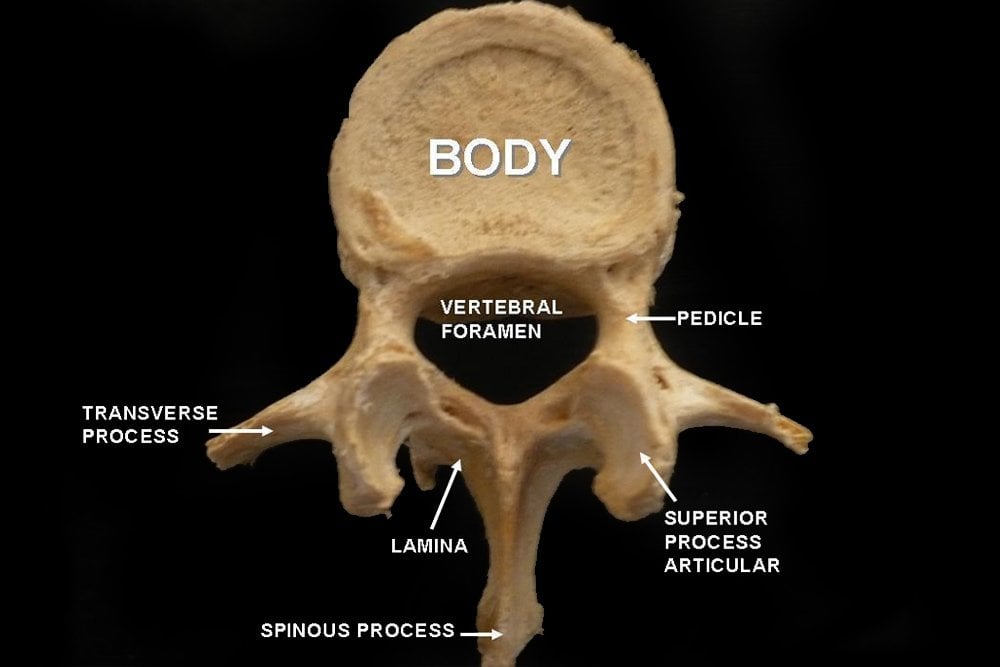

The typical structure of a vertebra is illustrated below:

There is a part of the body, the vertebral foramen, where the spinal cord, the process that handles nerves from the brain, passes through. Several other processes exist in the vertebral bone, such as the spinous process, seen in the picture above. These processes are elongated, bony protrusions that help in association and articulation with muscles and other bones.

These are the largest vertebrae and have huge bodies. They bear the weight of the body and have a great capacity for movement. The orientation of their process is parasagittal (adjacent to the sagittal or longitudinal plane), which is supposedly responsible for their bending capacity. Spondylosis is most common is this region of the vertebral column.